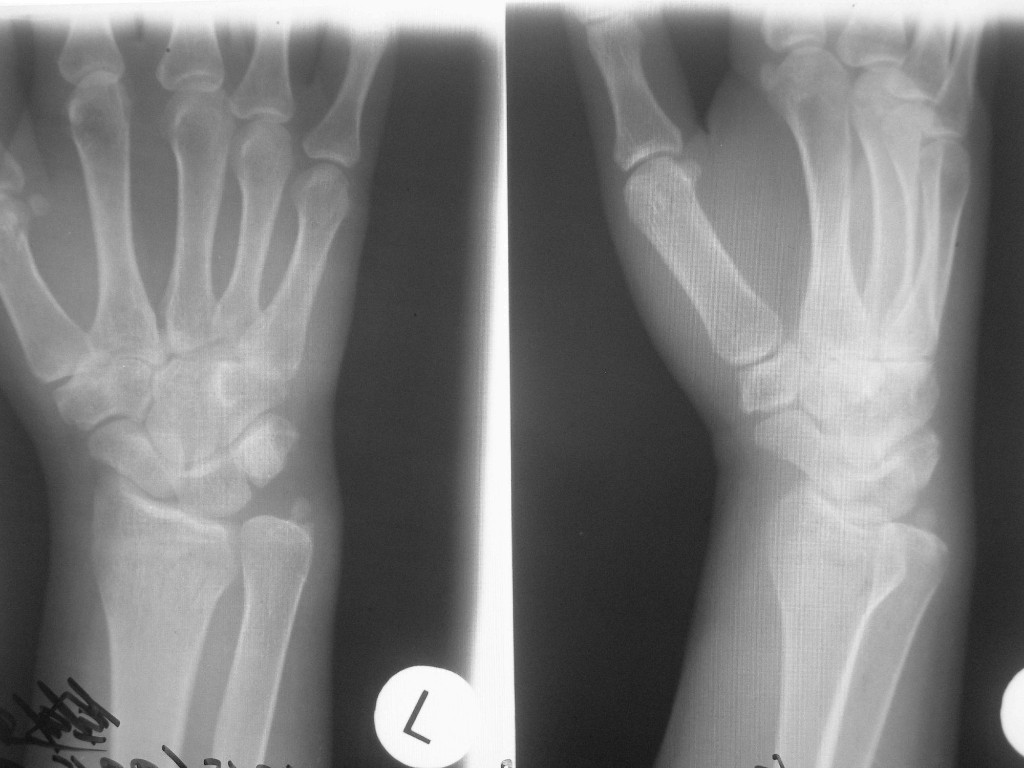

ТОКИО, 27 июл — РИА Новости. У олимпийского чемпиона по тхэквондо россиянина Максима Храмцова выявлено подозрение на перелом правой кисти руки, сообщается в официальном Telegram-канале Олимпийского комитета России (ОКР).

Храмцов, выступавший в весе до 80 кг, завоевал на Играх в Токио первую в истории российского тхэквондо золотую олимпийскую медаль. После победы в турнире россиянин сообщил, что еще в первом бою повредил руку, и по симптомам это было похоже на перелом. Также он ранее сломал руку в мае на чемпионате Европы.»Максима Храмцова, олимпийского чемпиона по тхэквондо, подозрение на внутрисуставной перелом на уровне II запястно-пястного сустава правой кисти. Врачом травматологом-ортопедом Максимом Величко выполнена гипсовая иммобилизация, планируется дополнительное обследование. Прогноз для спортивной карьеры благоприятный», — говорится в сообщении.

Храмцов, выступавший в весе до 80 кг, завоевал на Играх в Токио первую в истории российского тхэквондо золотую олимпийскую медаль. После победы в турнире россиянин сообщил, что еще в первом бою повредил руку, и по симптомам это было похоже на перелом. Также он ранее сломал руку в мае на чемпионате Европы.

«Максима Храмцова, олимпийского чемпиона по тхэквондо, подозрение на внутрисуставной перелом на уровне II запястно-пястного сустава правой кисти. Врачом травматологом-ортопедом Максимом Величко выполнена гипсовая иммобилизация, планируется дополнительное обследование. Прогноз для спортивной карьеры благоприятный», — говорится в сообщении.